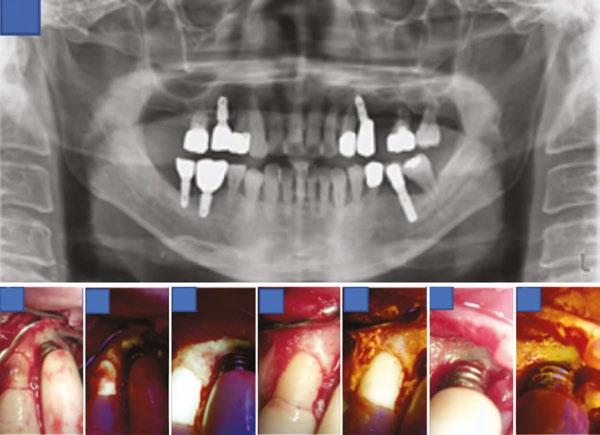

Clinical examination revealed probing depths of 5–6 mm around implant Nos. 4 and 5, with thread exposure at implant No. 5 above the gingival margin. Radiographic examination revealed bone loss around implant Nos. 4 and 5, leading to a diagnosis of peri-implantitis (Figure 3A). Although no significant biofilm accumulation was visible to the naked eye (Figure 3B), evaluation using QLF clearly detected biofilm that was not observable under conventional visual inspection (Figure 3C). Considering the patient’s osteoporosis and the fact that only 4 months had passed since her last denosumab (Prolia®) injection, flap surgery was not performed. Instead, curettage was selected as the treatment approach.

For biofilm removal, cleansing was performed using an ultrasonic scaler (Megagen, Seoul, South Korea), a curette, and a microbrush. After mechanical debridement, QLF imaging was conducted again to compare pre- and post-treatment findings. While no biofilm was visible to the naked eye (Figure 3D), QLF revealed residual biofilm on the implant threads (Figure 3E). Additional debridement was carried out, followed by another round of clinical and QLF imaging for confirmation (Figures 3F-3G). This process enabled a more thorough evaluation of biofilm removal and served as a visual aid for patient education on oral hygiene. Targeted brushing instruction (TBI) was also provided.

Clinical examination revealed a probing depth of 5–6 mm around implant No. 20, with the implant threads exposed above the gingiva. Although no significant biofilm attachment was observed with the naked eye (Figure 4B), QLF revealed the presence of biofilms (Figure 4C). In addition, periapical radiography revealed bone loss around implant No. 20, leading to a diagnosis of peri-implantitis (Figure 4A). Despite her dental phobia, the patient consented to undergo flap surgery after a thorough explanation of the necessity of actively removing factors contributing to infection from the implant surface.

#12 blades. Upon flap elevation, visible biofilm was observed (Figure 4D), and its presence was confirmed with QLF imaging (Figure 4E). Biofilm removal was performed using an ultrasonic scaler (Megagen, Seoul, South Korea), a curette, and a microbrush. Tetracycline was additionally applied for implant surface decontamination. Subsequent clinical and QLF imaging confirmed the successful removal of residual biofilm and infectious material (Figure 4F-4G). The surgical site was then closed using 4-0 absorbable synthetic sutures (Coated Vicryl™, Ethicon, Johnson & Johnson, Somerville, New Jersey) with an interrupted suture technique.

Clinical examination revealed a probing depth of 12 mm around implant No. 19, accompanied by active pus discharge above the gingival margin (Figure 5C). Furthermore, QLF imaging detected red fluorescence from porphyrins, indicating a mature biofilm (Figure 5D). Cone-beam computed tomography revealed bone loss around implant Nos. 18 and 19, leading to a diagnosis of peri-implantitis (Figures 5A-5B). Notably, implant

No. 19 exhibited bone loss extending to the apex, and during prosthesis removal, it was spontaneously exfoliated (Figure 5E). Although no significant biofilm was observed macroscopically on the tissue and fixture surfaces (Figure 5G), QLF evaluation detected porphyrin fluorescence, confirming the presence of a biofilm (Figures 5F-5H).

Clinical examination revealed a subgingival calculus at site tooth No. 11 and a probing depth of 6 mm at site implant No. 12. Furthermore, based on the panoramic radiography findings, the prognosis of tooth No. 14 was hopeless (Figure 6A); therefore, extraction of tooth No. 14 and flap surgery for implant No. 12 were planned. An intrasulcular incision was made from the mesial line angle of tooth No. 10 to the distal aspect of implant No. 12 using #15T and #12 blades. After flap elevation, subgingival calculus and bone loss were confirmed around tooth No. 11 and implant No. 12, respectively (Figure 6B).

Although no biofilm was visible to the naked eye on the implant No. 12 threads, QLF imaging revealed its presence (Figure 6C). Biofilm removal was performed using an ultrasonic scaler (Megagen, Seoul, South Korea), curette, and microbrush. Follow-up QLF imaging was conducted to evaluate the pre- and post-treatment difference, confirming successful biofilm removal (Figure 6D). The area was irrigated with tetracycline, and additional clinical photographs and QLF images were taken to verify the elimination of biofilm and infection at tooth No. 11 and implant No. 12 (Figures 6E-6H). Interrupted sutures were placed using 4-0 absorbable synthetic sutures (Coated Vicryl™, Ethicon, Johnson & Johnson, Somerville, USA). The importance of oral hygiene management was emphasized using visual aids, and tooth brushing instruction (TBI) was provided.